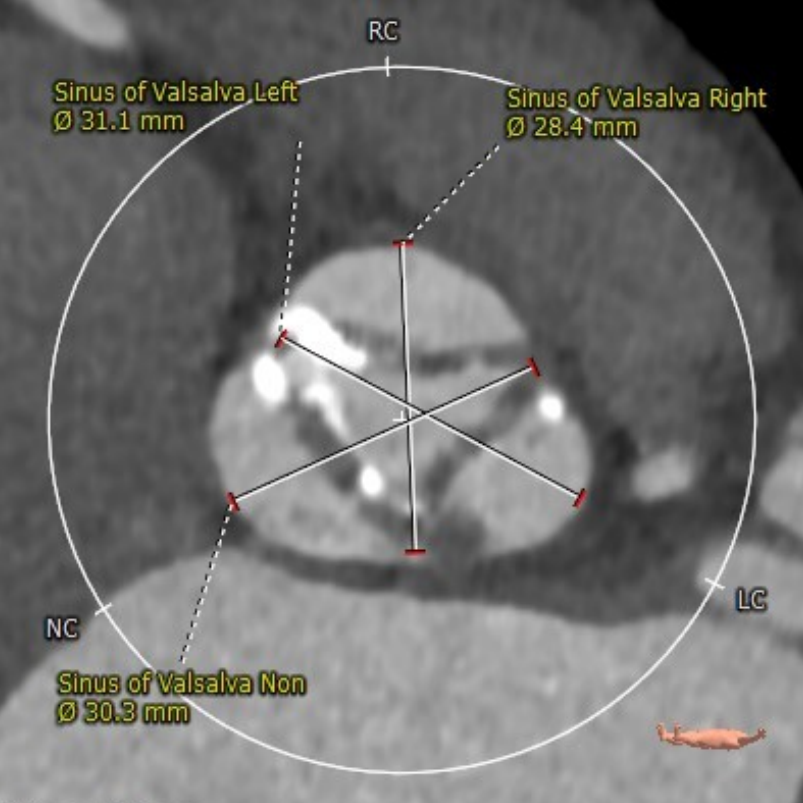

法氏窦

直径:25.3*24.2*25.1mm

左冠高度高度:14.6mm

右冠高度高度:9.8mm

主动脉瓣角度 44°

钙化积分68mm³

右冠